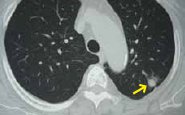

⑧胸部(肺)CT

肺を細かく撮影することで、X線写真では分からない極めて小さな肺癌、心臓や肋骨などの陰に隠れた肺癌などを発見することができます。肺癌の発見率が胸部X線の約10倍高いとされています。